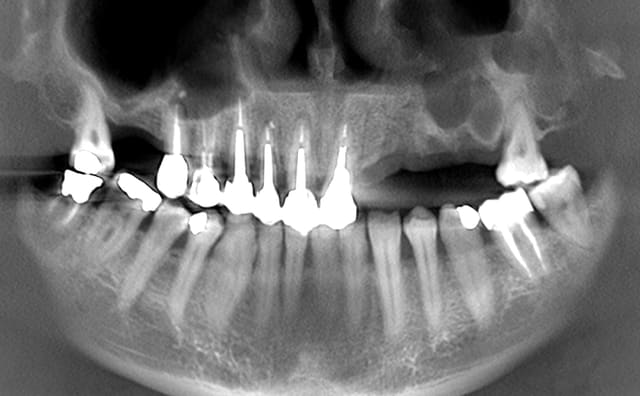

votre avis sur un cas vu today

le Monsieur veut absolument une solution fixe

14344 pano ecglox - Eugenol

Bon plus sérieux :

1-L'occlusion est moche

2-Les dents post sup sont très moche

3-Besoin de 2 sinus lift

4-Faut tout refaire les zones post.inf.

5-Esthétique ? Jolies les CCM en haut ???

6-Place implants en haut après les sinus et exo des 7

7-Il te reste à faire les secteurs antérieurs.

Tu peux aussi tout virer en haut, 2 sinus, max d'implants et une ré-hab du haut sur implants (oubli pas le bas, l'occlusion, etc.).

t'as vu la gueule du sinus ....... il c'est passé quoi ?

Alvéolectomie à la fraise résine ?????

Tumeur ?

dis nous en un peu plus

dixit le patient: "j'ai eu des dents arrachées il y a une quinzaine d'années avec une grosse infection et des kystes et j'ai eu une communication avec le sinus"

pour remplacer de 22 à 26 j'ai 38 mm d'arcade soit 22-23-24-25 et une 3ème prémolaire.

pour 22-23 hauteur osseuse ok, un petit manque en épaisseur pour 23, pour les prémolaires faudrait que la cavité remplie de tissu mou soit ossifiée.

- dissection sous la muqueuse vestibulaire et sous le sinus avec curetage complet de la cavité et rerait du petit bout de racine résiduel

- membrane sous le sinus, comblement de la cavité et membrane en vestibulaire

- attente d'ossification

- implantation

çà risque d'être très chaud quand même (la dissection et le curetage complet dans les petits recoins)

vos avis?

J'ai peur pour le bridge anterieur:

13 parois residuelles trop fines

12 sensation de fracture radiculaire mesiale

21 tres fragile

Alors toucher ou pas?Considerer le bloc anterieur comme un plan de traitement different du reste a traiter plus tard?